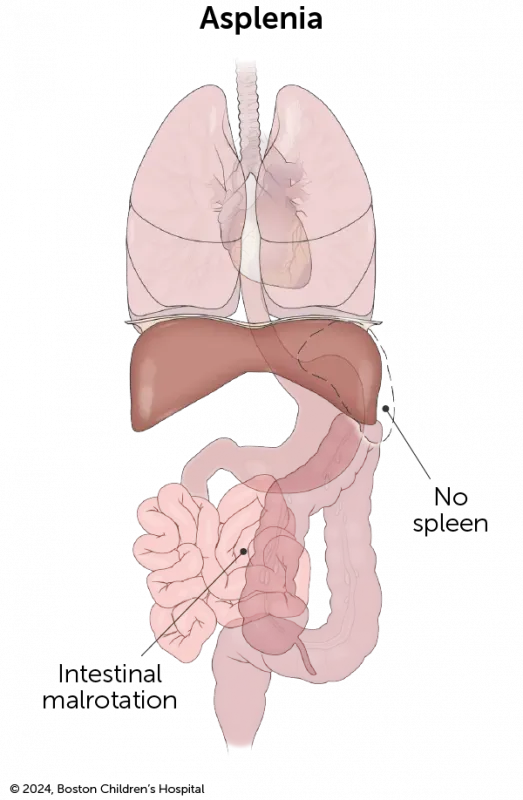

Check out our downloadable pamphlet for a summary about heterotaxy syndrome. It provides details about the diagnosis, testing, treatment at Boston Children’s, and more.